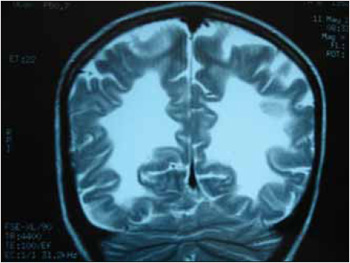

RNM corte coronal. Observa-se imagem em asa de mariposa em ambos os hemisférios.

A adrenoleucodistrofia (ADL) é uma doença genética com padrão de herança ligado ao X , que consiste numa alteração do metabolismo dos peroxissomos, ocasionando um acúmulo de ácidos graxos de cadeia muito longa (AGCML) constituídos de 24 e 26 átomos de carbono no organismo sobretudo no cérebro e nas glândulas adrenais. Tal acúmulo está associado à desmielinização dos axônios afetando a transmissão dos impulsos nervosos e a insuficiência adrenal. Afeta quase exclusivamente o sexo masculino com início dos sintomas entre 4 e 10 anos e incidência estimada de 1:25000 homens. A manifestação clínica da doença consiste inicialmente em alterações de comportamento, da audição, da visão, da fala, da escrita, memória, da marcha, distúrbios adrenais e nos casos mais avançados cursa com hipertonia generalizada, perda das funções cognitivas, motoras, convulsões e disfagia. O diagnóstico é confirmado dosando-se os níveis plasmáticos dos AGCML, Ressonância Magnética mostrando lesões desmielinizantes com distribuição em "asa de mariposa" na substância branca parieto-occipital bi-hemisférica, eletromiografia compatível com polineuropatia tipo mielinopático, pesquisa laboratorial para insuficiência adrenal e cariótipo cujo gene defeituoso é o ABCD1 localizado no lócus X9-28 do cromossomo X (2, 3, 4,5,6).

Outros sinais como disartria, dismetria , bradilalia, disgrafia ou alterações na marcha apontarão para a hipótese de doença neurodegenerativa a qual deve ser investigada e diagnosticada. Na ADL o diagnóstico é auxiliado pela Ressonância Magnética que mostra lesões desmielinizantes com distribuição em asa de mariposa na substância branca parieto-occipital bi-hemisférica, dosagem dos níveis plasmáticos dos AGCML aumentados, eletromiografia compatível com polineuropatia tipo mielinopático, pesquisa laboratorial para insuficiência adrenal e cariótipo. Após o diagnóstico é importante uma equipe multiprofissional para acompanhamento e reabilitação desses doentes já que se trata de uma doença evolutiva. Em fases mais avançadas cursam com graus variados de disfagia neurogênica diagnoticadas através de videoendoscopia da deglutição ou videodeglutograma. A terapia nestes estágios consiste em manobras de deglutição ou gastrostomia se alimentação oral não é segura ou inadequada.